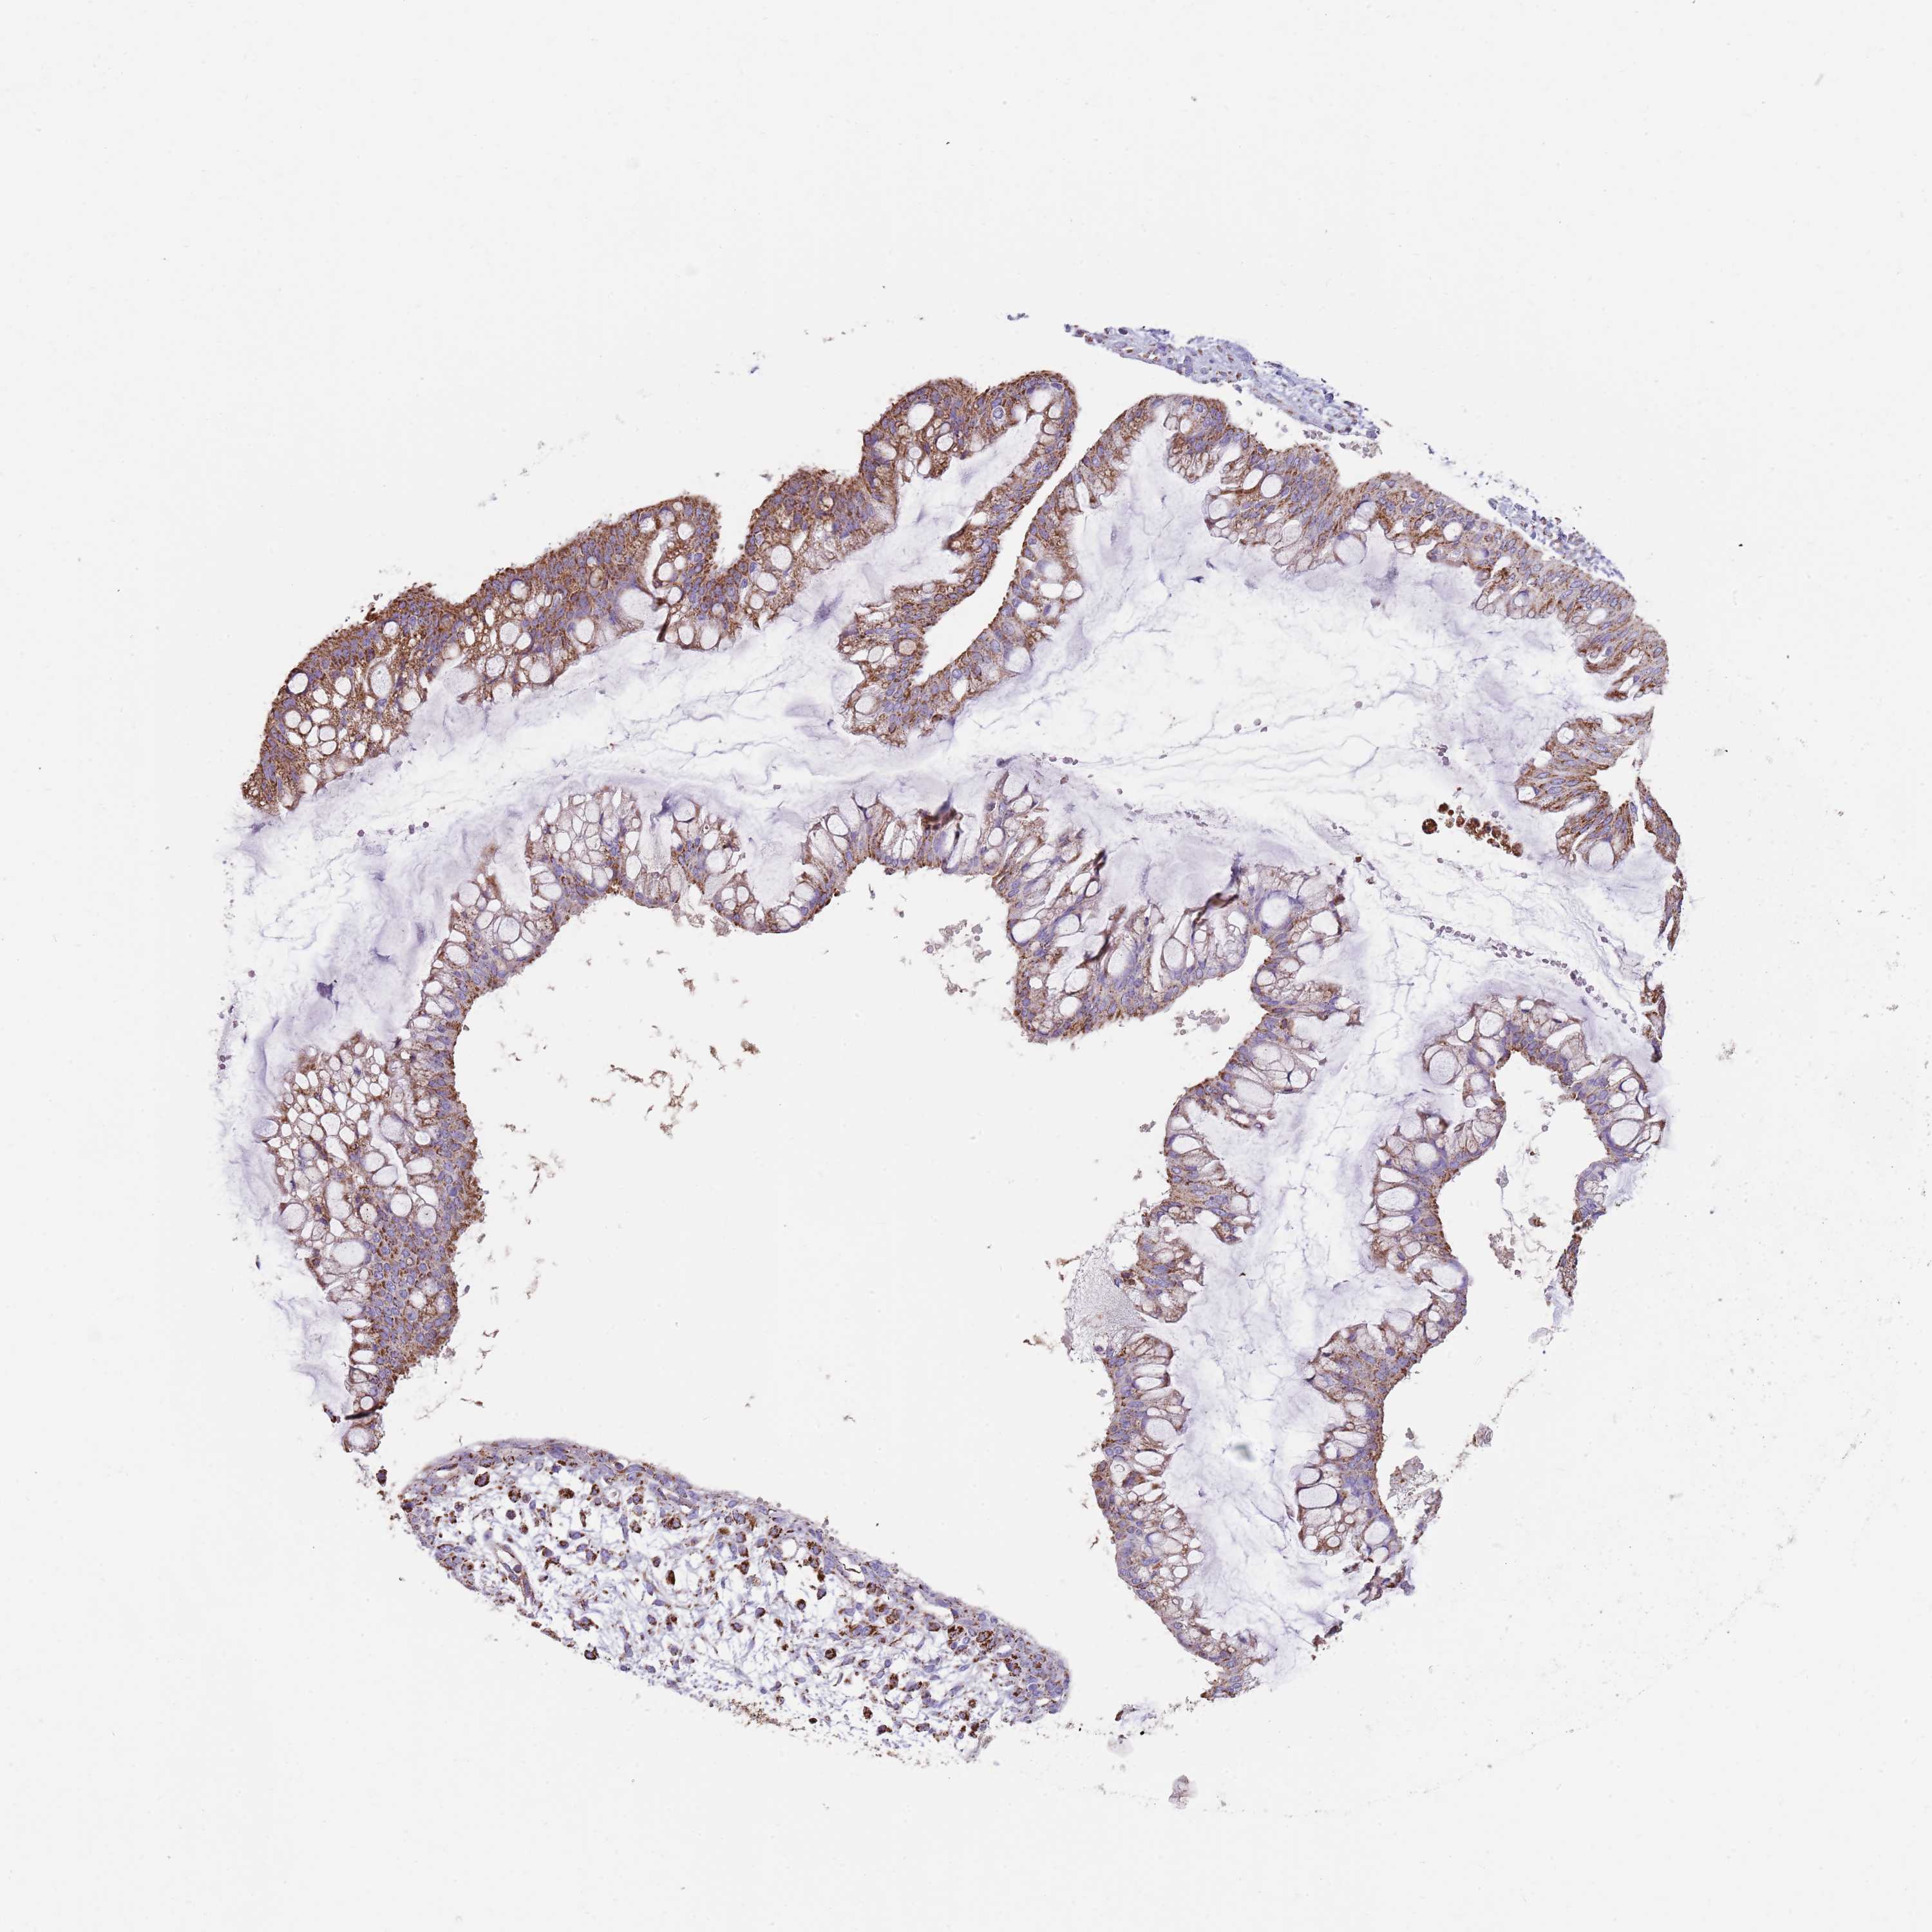

OVARIAN CANCER - Protein expressioni

A mouse-over function shows sample information and annotation data. Click on an image to view it in a full screen mode. Samples can be filtered based on level of antibody staining by selecting one or several of the following categories: high, medium, low and not detected. The assay and annotation is described here.

Note that samples used for immunohistochemistry by the Human Protein Atlas do not correspond to samples in the TCGA dataset.

Antibody stainingi

Antibody staining in the annotated cell types in the current human tissue is reported as not detected, low, medium, or high, based on conventional immunohistochemistry profiling in selected tissues. This score is based on the combination of the staining intensity and fraction of stained cells.

Each image is clickable and will lead to virtual microscopy that enables deeper exploration of all samples and also displays staining intensity scores, fraction scores and subcellular localization as well as patient and tissue information for each sample.

Antibody HPA048392

Staining

High

Medium

Low

Not detected

Intensity

Strong

Moderate

Weak

Negative

Quantity

>75%

75%-25%

<25%

None

Location

Nuclear

Cytoplasmic/membranous

Cytoplasmic/membranous,nuclear

Cystadenocarcinoma, serous, NOS

Carcinoma, NOS

Cystadenocarcinoma, mucinous, NOS

Carcinoma, endometroid